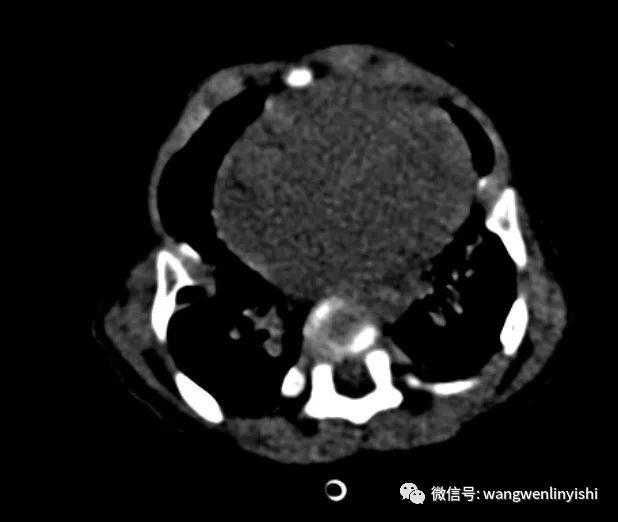

The patient, a nine-month-old infant, exhibited a chest wall abnormality along with pronounced breathing difficulties and hypoxia shortly after birth. After a series of examinations, he was diagnosed with asphyxiating thoracic dystrophy(ATD). Due to his critical condition, the child has been hospitalized for emergency resuscitation multiple times.

The infant is breathing rapidly, displaying distinct retractions in the suprasternal notch, supraclavicular fossae, and intercostal spaces (three concave signs). The chest appears narrowed, and there are visible depressions on both sides.